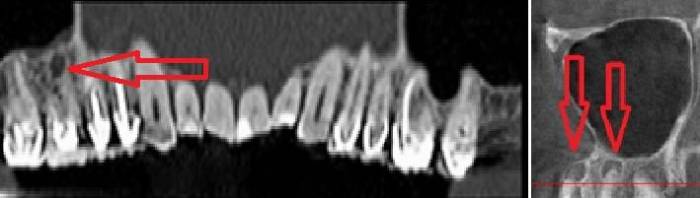

Стрелками показаны фрагменты пломбировочного материала (вид спереди и сбоку), который при пломбировании канала выпал за пределы зуба и «упёрся» в область залегания ветви тройничного нерва. У пациента долго болел зуб после лечения пульпита, затем онемела верхняя губа и часть щеки.

Вариант 2. Киста корня зуба раздражает ветвь тройничного нерва. Боль и онемение губы и щеки, боль при накусывании.